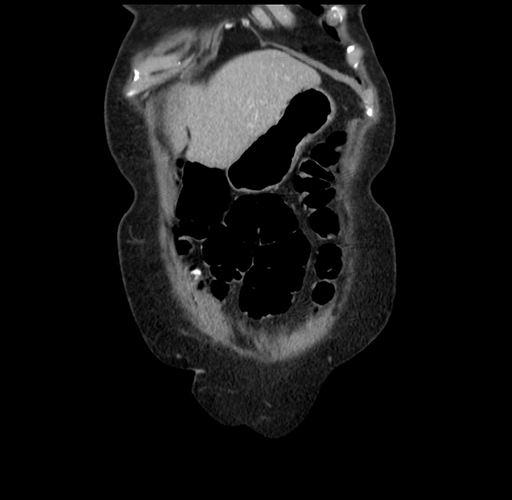

Pre-Chemo: Axial Venous

Axial Venous